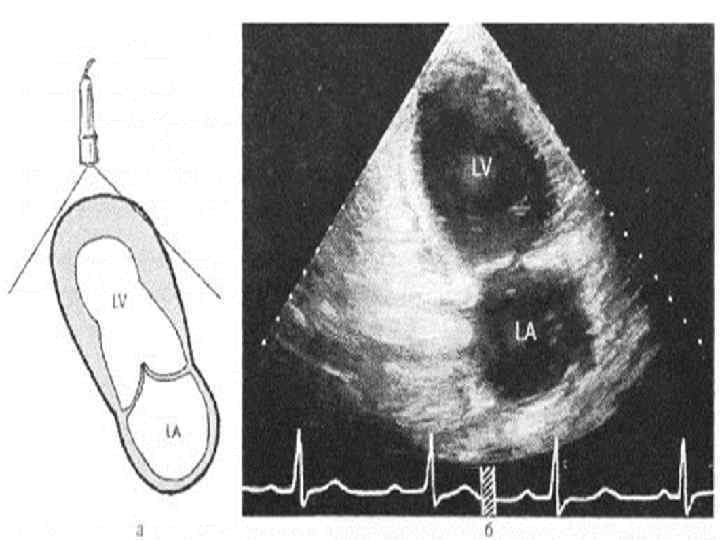

Ультразвуковая анатомия сердца В эхокардиографии используют ряд доступов к сердцу и магистральным сосудам: • Левый парастернальный • Апикальный • Субкостальный • Супрастернальный • Правый парастернальный